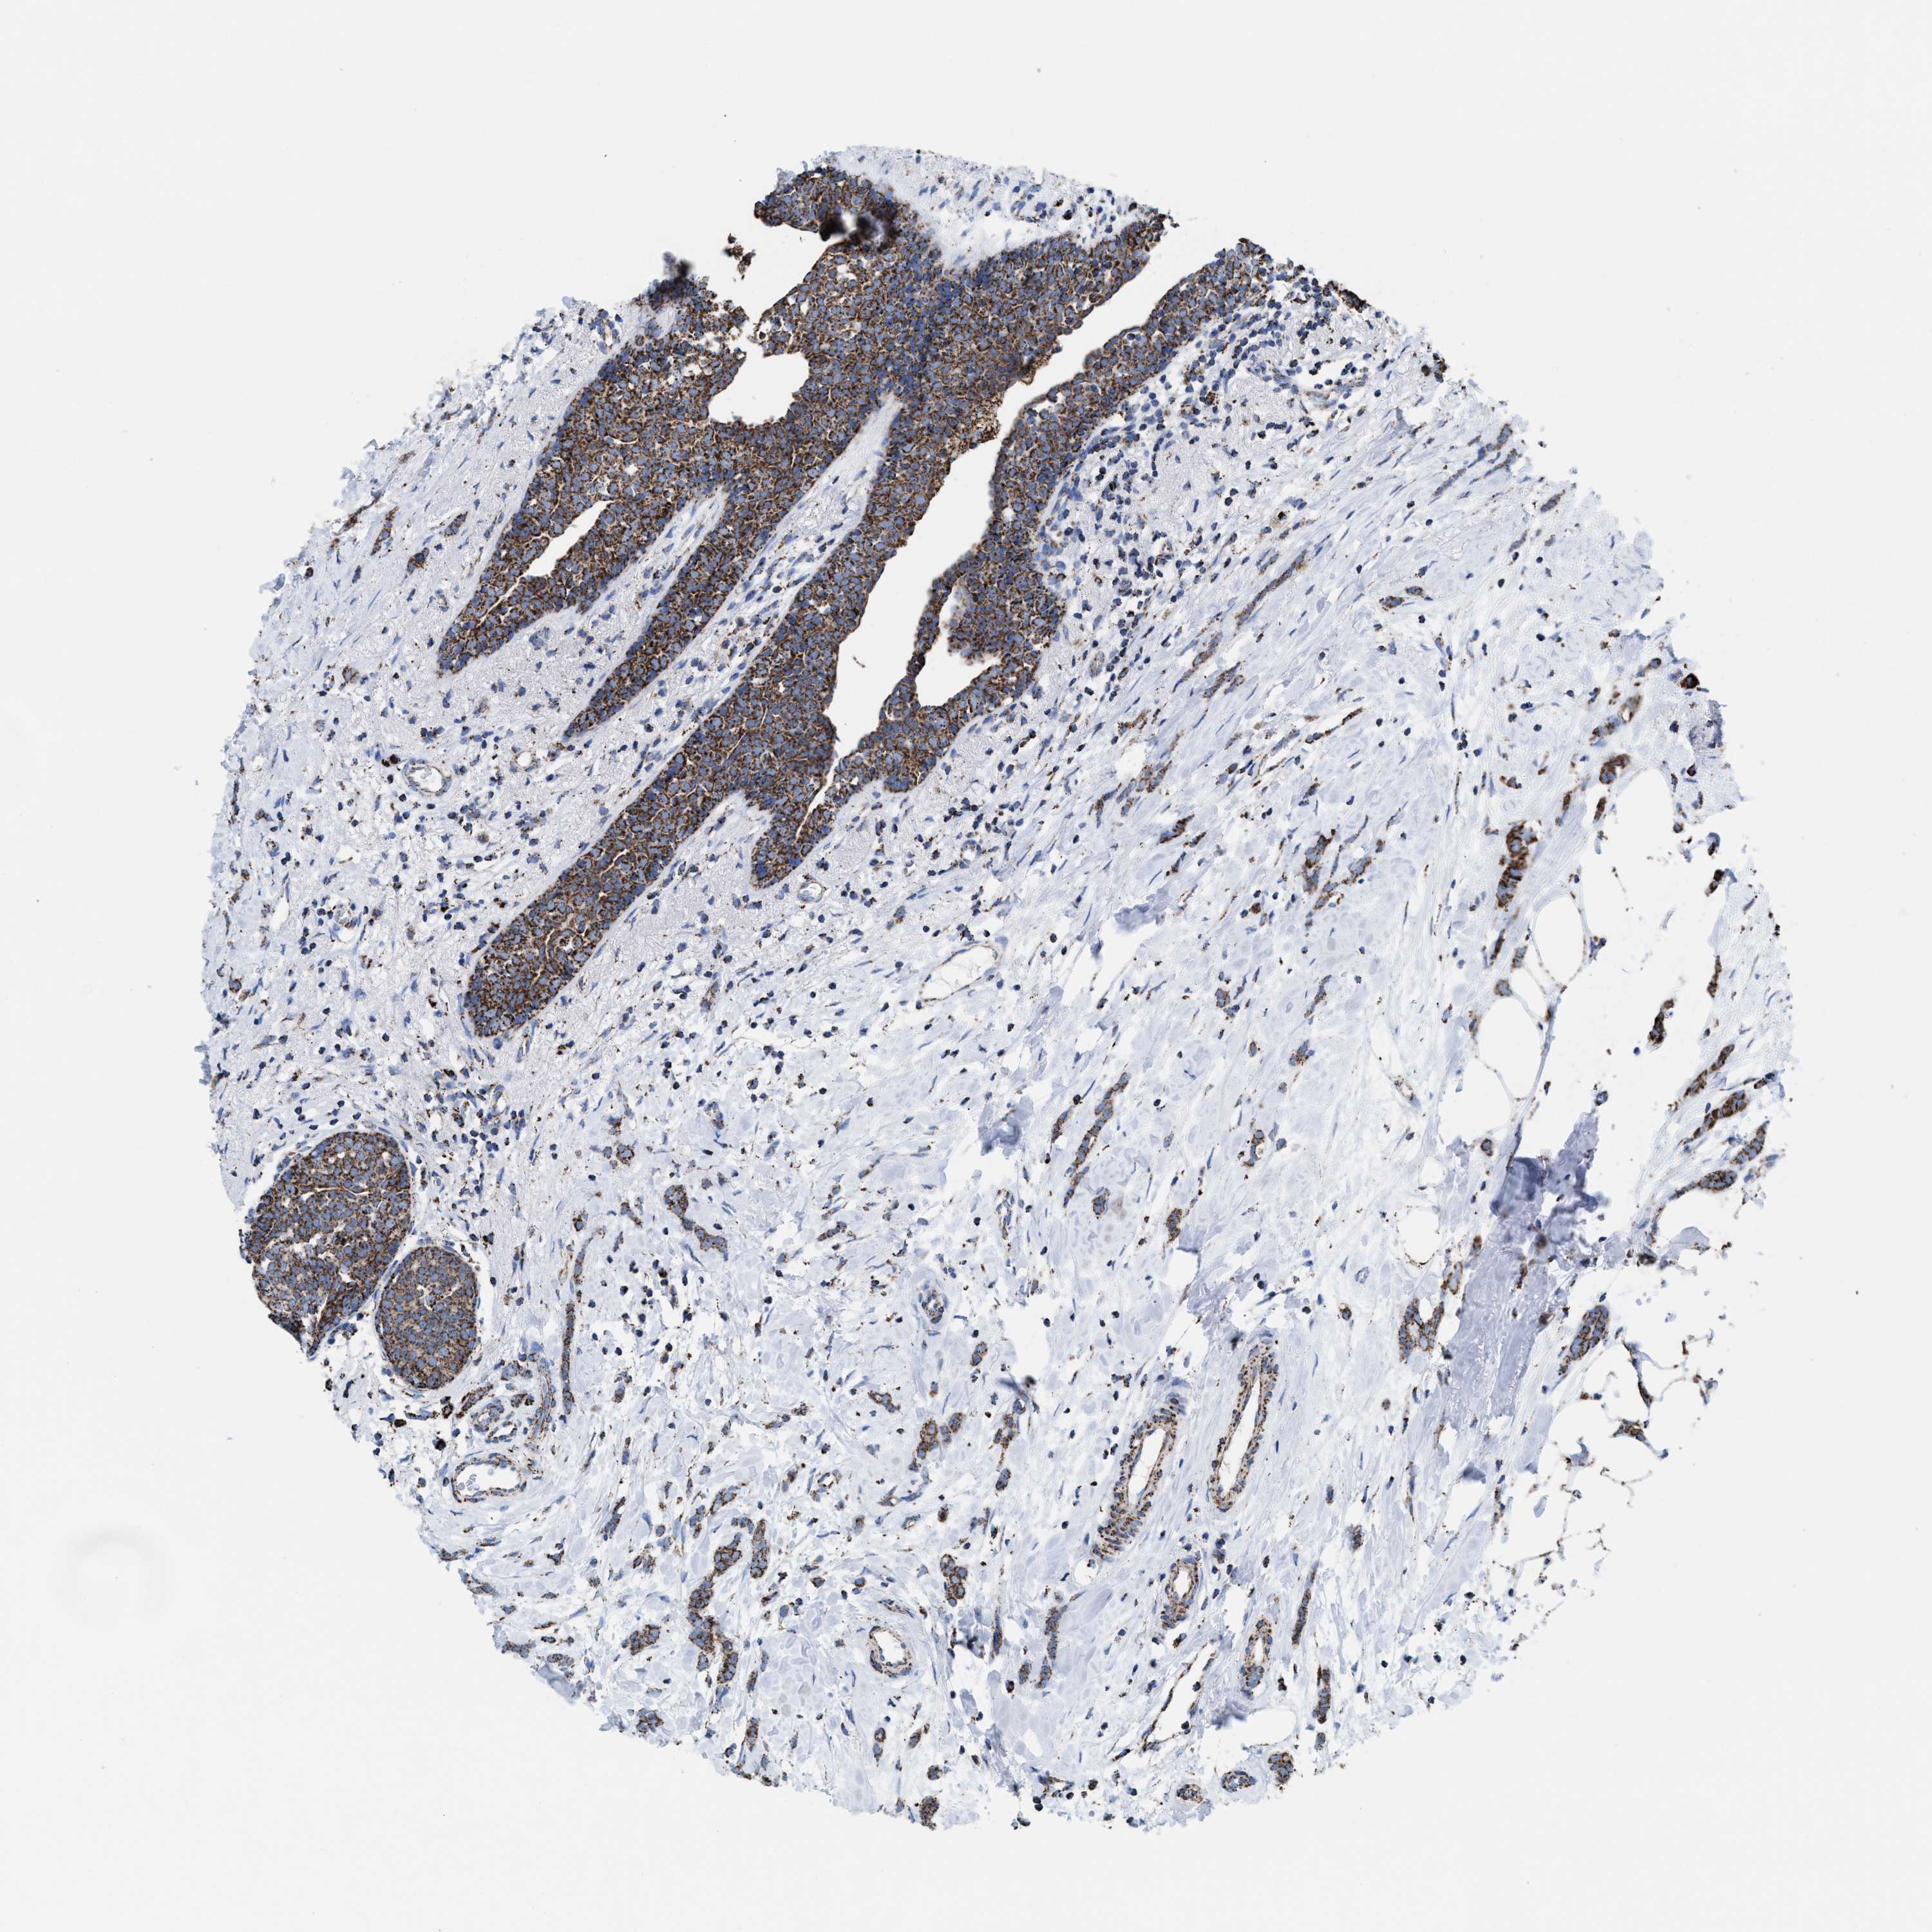

CANCER BREAST CANCER Show tissue menu

BRCA TCGA BRCA VALIDATION PROTEIN EXPRESSION

Breast cancer

Human cancer